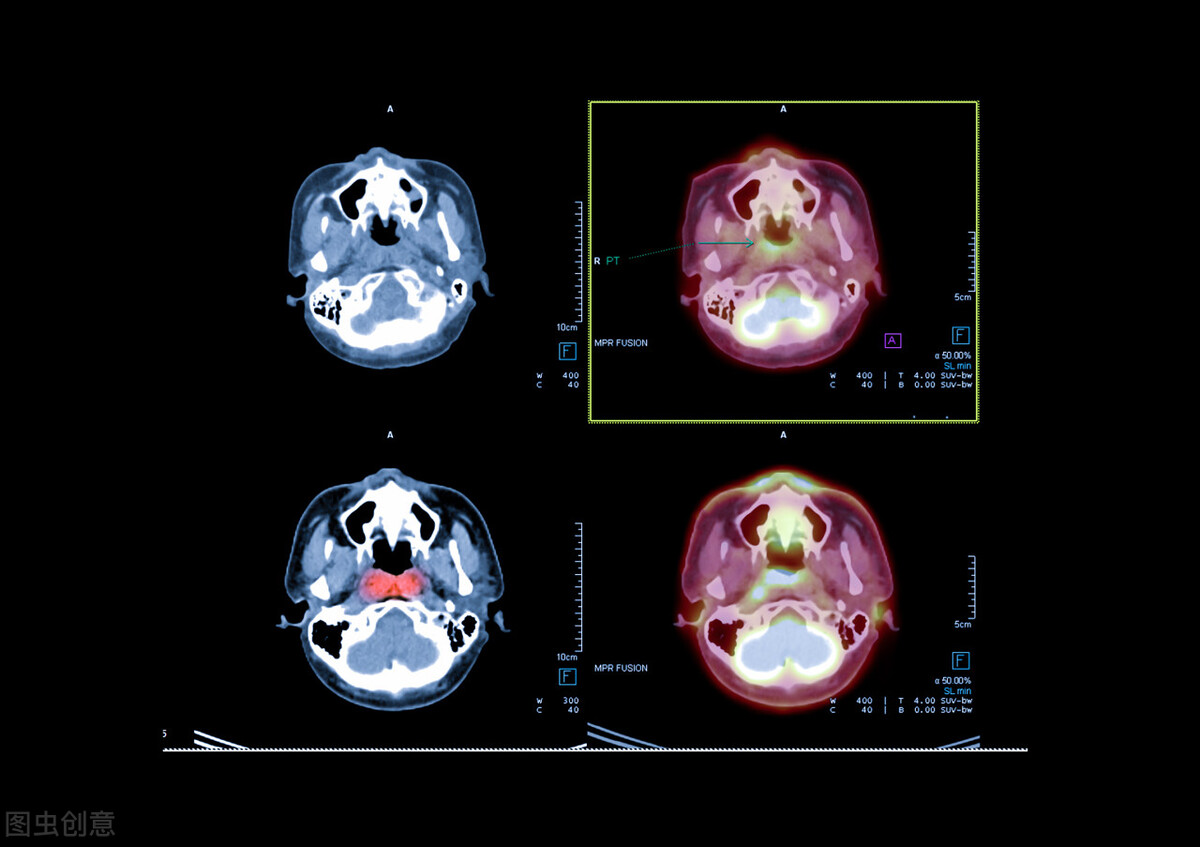

患者一年前偶感涕中带血及听力下降,以为当时天气干燥,自己也经常熬夜,偶然情况也并未在意,且未进一步到院检查;直至半年前症状越来越明显,还伴有头痛、头晕,到院就诊后,发现鼻咽部新生物,鼻内镜下行鼻咽部新生物活检,病检提示鼻咽癌;今到院进一步治疗,查体情况如下:左侧颈部可触及 约5×6cm大小肿块,表面不光滑,压痛明显,质地硬,结合患者所提供的影像资料,目*考前**虑为鼻咽癌伴颈部淋巴结转移。

患者诊断明确分期比较晚,但是鼻咽部对放射治疗敏感,通过同步放化疗病情是可以得到很好的控制,就患者情况 针对鼻咽部病灶Dt:70.62Gy/33f,颈部淋巴结转移病灶Dt:Dt:7029cGy/33f,及颈部高危淋巴引流区Dt:6006cgyGy/33、低危淋巴引流区Dt:5012cgy/28f,放疗期间予顺铂40mg同步增敏化疗联合治疗。

值得可喜的是,在放疗20次之后复查鼻咽CT,鼻咽部病灶缩小。整个治疗过程也顺利完成,建议患者半月后返院行全身化疗治疗,一般采用顺铂+5-氟尿嘧啶等方案,4周期,3-4周为一个周期。